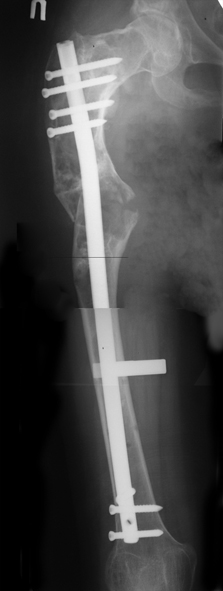

Уважаемые коллеги! С Новым годом и самых светлых пожеланий!В ноябре этого года я обращался с просьбой о помощи в выборе тактики лечения больной с деформацией бедра на почве фиброзной дисплазии. Были получены интересные и очень полезные советы по операции.

Хотелось бы показать, что получилось в результате.Операция выполнялась с помощью А.Н.Челнокова. Очень понравилась технология выполнения блокируемого остеосинтеза с использованием спицевого дистрактора, модифицированный гвоздь с латерализованным проксимальным отделом и возможностью многовинтовой фиксации проксимального и дистального участков бедра.

Прекрасная работа, поздравляю Александра и Леонида с удачной реконструкцией: длины и контура бедра.